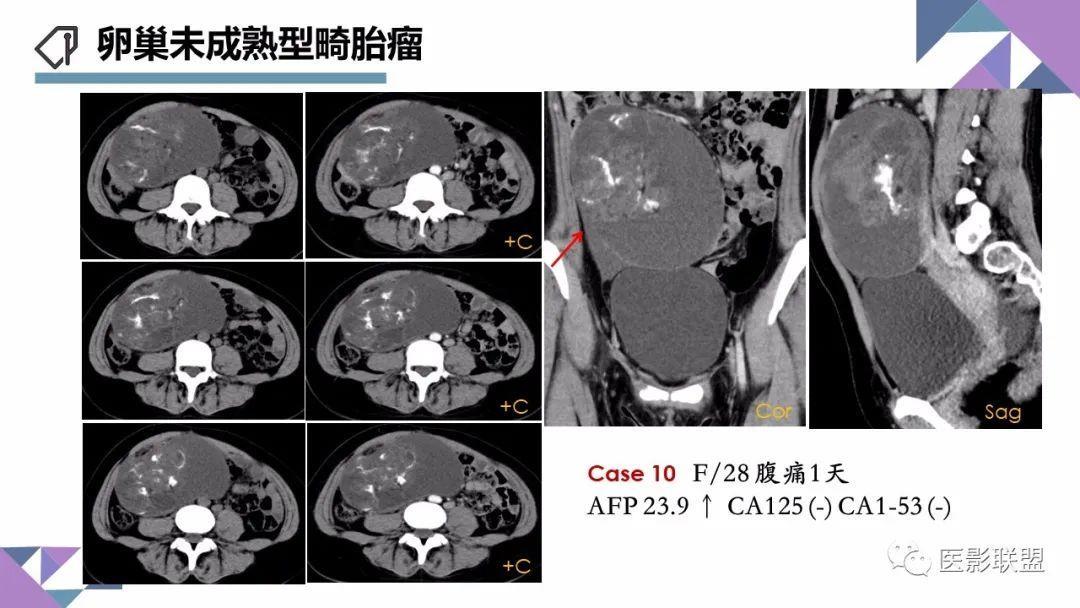

卵巢畸胎瘤的图像诊断及不典型征象分析

作者:刘红艳 清远市人员医院